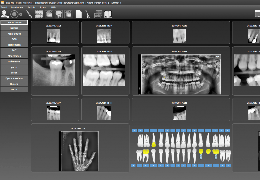

Load DICOM data directly from PACS, CD/DVD, USB, and local computer.

Upload DICOM data to your PACS directly from referral patient CD/DVD and local computer.

Easy to use patient search to locate patient data on your PACS.

Loads common non-DICOM file formats: NifTi (.nii), Visualization Toolkit (.vtk), and ANALYZE (.hdr).

Designed mainly for CT and MR DICOM modalities.